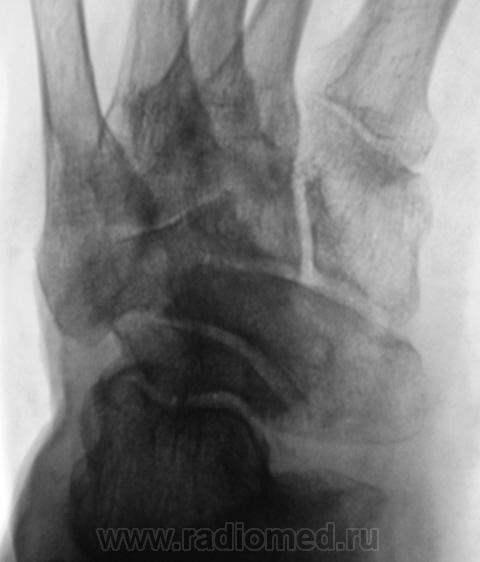

Две стопы - две сестры. Хозяин один.

Неспецифический (остеоартроз)?..

А, может это врожденное?